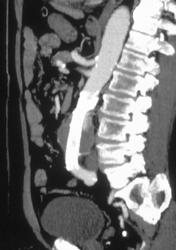

Aortic Dissection